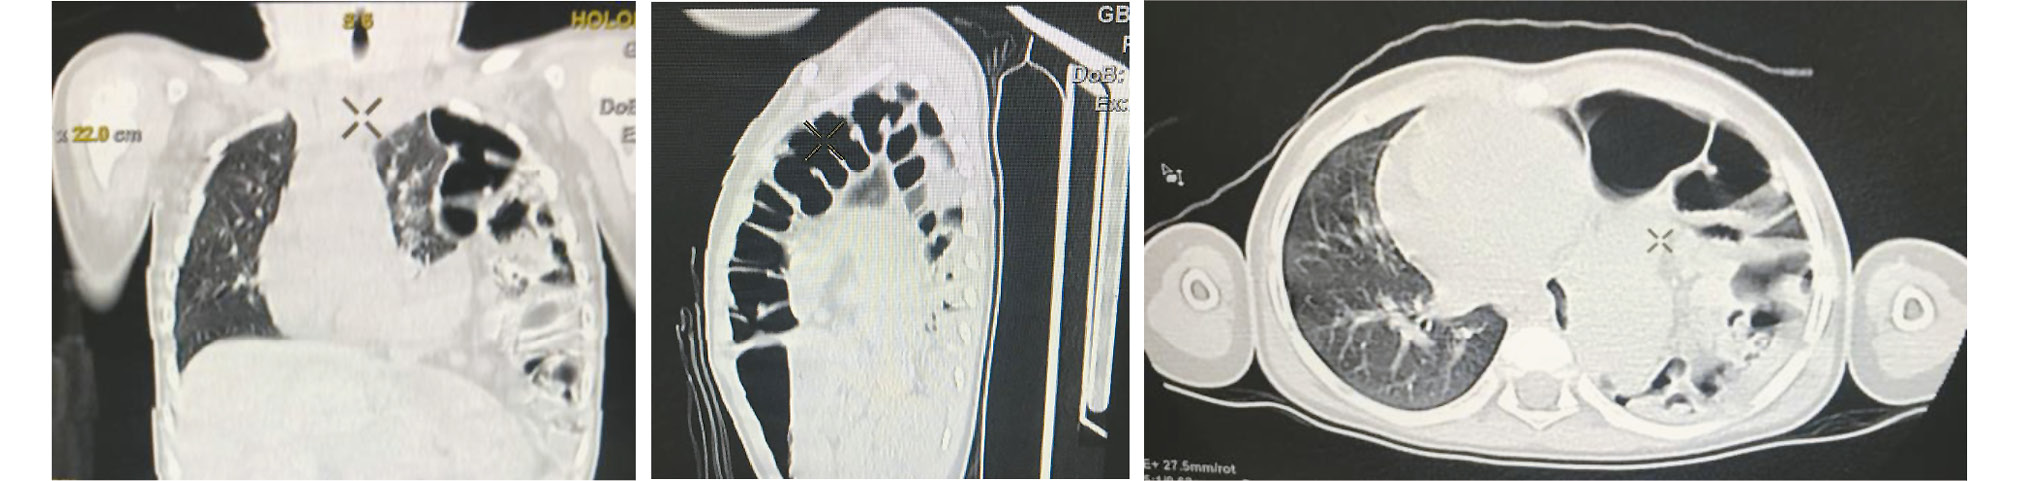

При рентгенологическом обследовании органов грудной клетки, выполненном впервые в июне 2022 года в 3-летнем возрасте, выявлены петли кишечника, лоцируемые в левой половине грудной полости (рис. 1).

Рис. 1. Обзорная рентгенограмма (прямая проекция): грыжа левого купола диафрагмы (указана стрелкой).

Fig. 1. Plain-film X-ray (direct projection): hernia of the left diaphragm dome (indicated by the arrow).